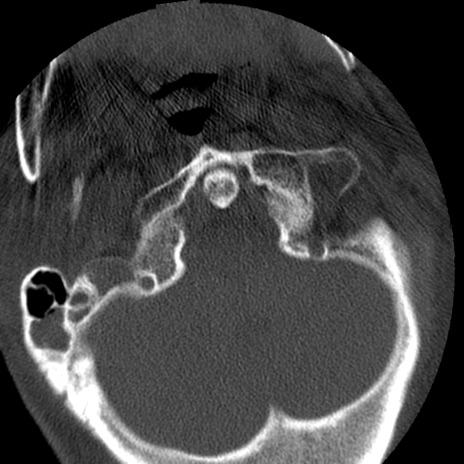

症例50 頚椎CT(横断像)

頚椎CT